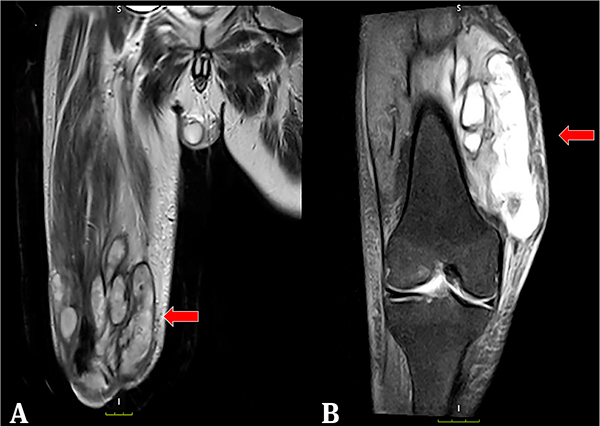

Presentación del caso: hombre de 61 años, diabético y trasplantado renal, con historia de 1 año de lesión ulcerada en rodilla derecha, no dolorosa y secretante. Histopatológicamente se observaron hifas dematiáceas, con diagnóstico presuntivo de feohifomicosis. Ante la mala evolución clínica a pesar del uso de itraconazol, requirió inicio de anfotericina B y manejo quirúrgico, de donde se aisló en cultivo Cladophialophora spp., confirmando así el diagnóstico. Actualmente está recibiendo voriconazol, con mejoría satisfactoria.

Conclusiones: se presenta un caso de feohifomicosis tumoral en un paciente inmunosuprimido, con poca mejoría al uso de terapia sistémica, que requirió combinación con manejo quirúrgico para obtener mejores resultados.